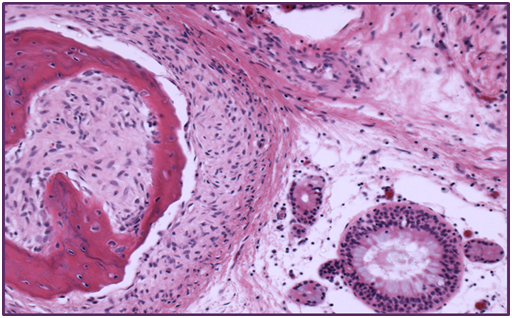

A 66 year old woman presented to the department of otolaryngology with complains of chronic headaches, rightnasal obstruction, and midfacial pain with a duration of 3 years. Clinical examination with a rigid endoscope revealed a polypoidal mass like structure in the right nasal cavity, extending from the middle turbinate to the posterior nasal space. CT and MRI depicted a soft tissue mass with calcification developing in the right nasal cavity, with no signs of bone erosion. The mass had a cephalocaudal diameter of 5 cm and a maximum anterior-posterior diameter of 3 cm extending from the level of the middle and superior turbinate back to the nasopharynx occluding partly the sphenoid sinus ostium. The maxillary and frontal sinuses were unremarkable. The patient underwent functional endoscopic sinus surgery with complete tumor resection. During surgery a small specimen was sent for frozen biopsy histopathological examination in order to exclude evidence of malignancy. Postoperative course was uneventful. The submitted specimen had a smooth hard surface with small irregular fragments of soft and bony tissue. Microscopic evaluation revealed an epithelial component consisting of islands of respiratory type epithelium with polypoid configuration forming invaginations into the subepithelial loose fibrovascular myxoid stromaadmixed with areas of immature fibrocartilaginous and bony tissue. No atypia or mitoses were observed or signs of infiltrative growth, excluding malignancy (Figure1 & 2).

Figure 2 Chondrofibromatous areas.